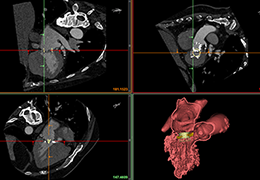

Segmentation

Segmentation of tissue (e.g., isolating the brain, differentiating gray and white matter) is performed using region-growing methods, filter operations as well as the application of 3D templates. Using the mouse it is very easy to explore a 3D volume with superimposed pseudocolor-coded statistical maps in a four-window representation showing a sagittal, coronal, transversal and oblique section. Based on a (segmented) 3D data set a three-dimensional reconstruction of the subjects' head and brain can be calculated and displayed from any specified viewpoint using volume or surface rendering.

Volume Rendering

Volume rendering is performed with a very fast ray casting algorithm; lightning calculations are based on Phong-shading. Surface rendering of reconstructed surfaces is performed using OpenGL. Using texture mapping, a reconstructed surface (e.g., head or brain) may be sliced in real time, showing both surface and volume data at the same time. Initial polygon meshes serve as the basis for surface finding, cortex inflation and cortex flattening computations.